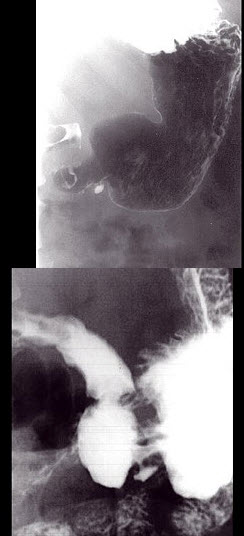

A.小儿及成人均可患病

男,24岁,中上腹痛,柏油样便,面色苍白,钡餐检查如图,可能的诊断为()

A.胃癌

B.胃溃疡伴良性狭窄

C.平滑肌肉瘤

D.胃间质瘤

E.胃淋巴瘤